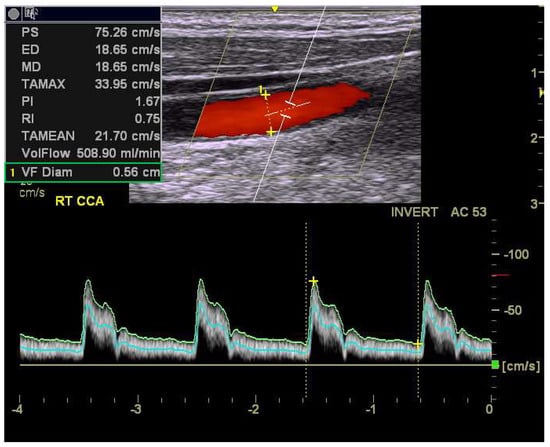

2.3. Ultrasonographic Measurements of Carotid Blood Flow

| Right CCA | Mean | SD | Mean | SD | |

| PSV (cm/s) | 86.2 | 20.2 | 79.6 | 19.4 | <0.0001 |

| EDV (cm/s) | 23.4 | 6.4 | 20.1 | 6.4 | <0.0001 |

| MFV (cm/s) | 40.7 | 9.2 | 35.8 | 9.2 | <0.0001 |

| RI | 0.73 | 0.06 | 0.75 | 0.06 | <0.0001 |

| PI | 1.57 | 0.36 | 1.70 | 0.39 | <0.0001 |